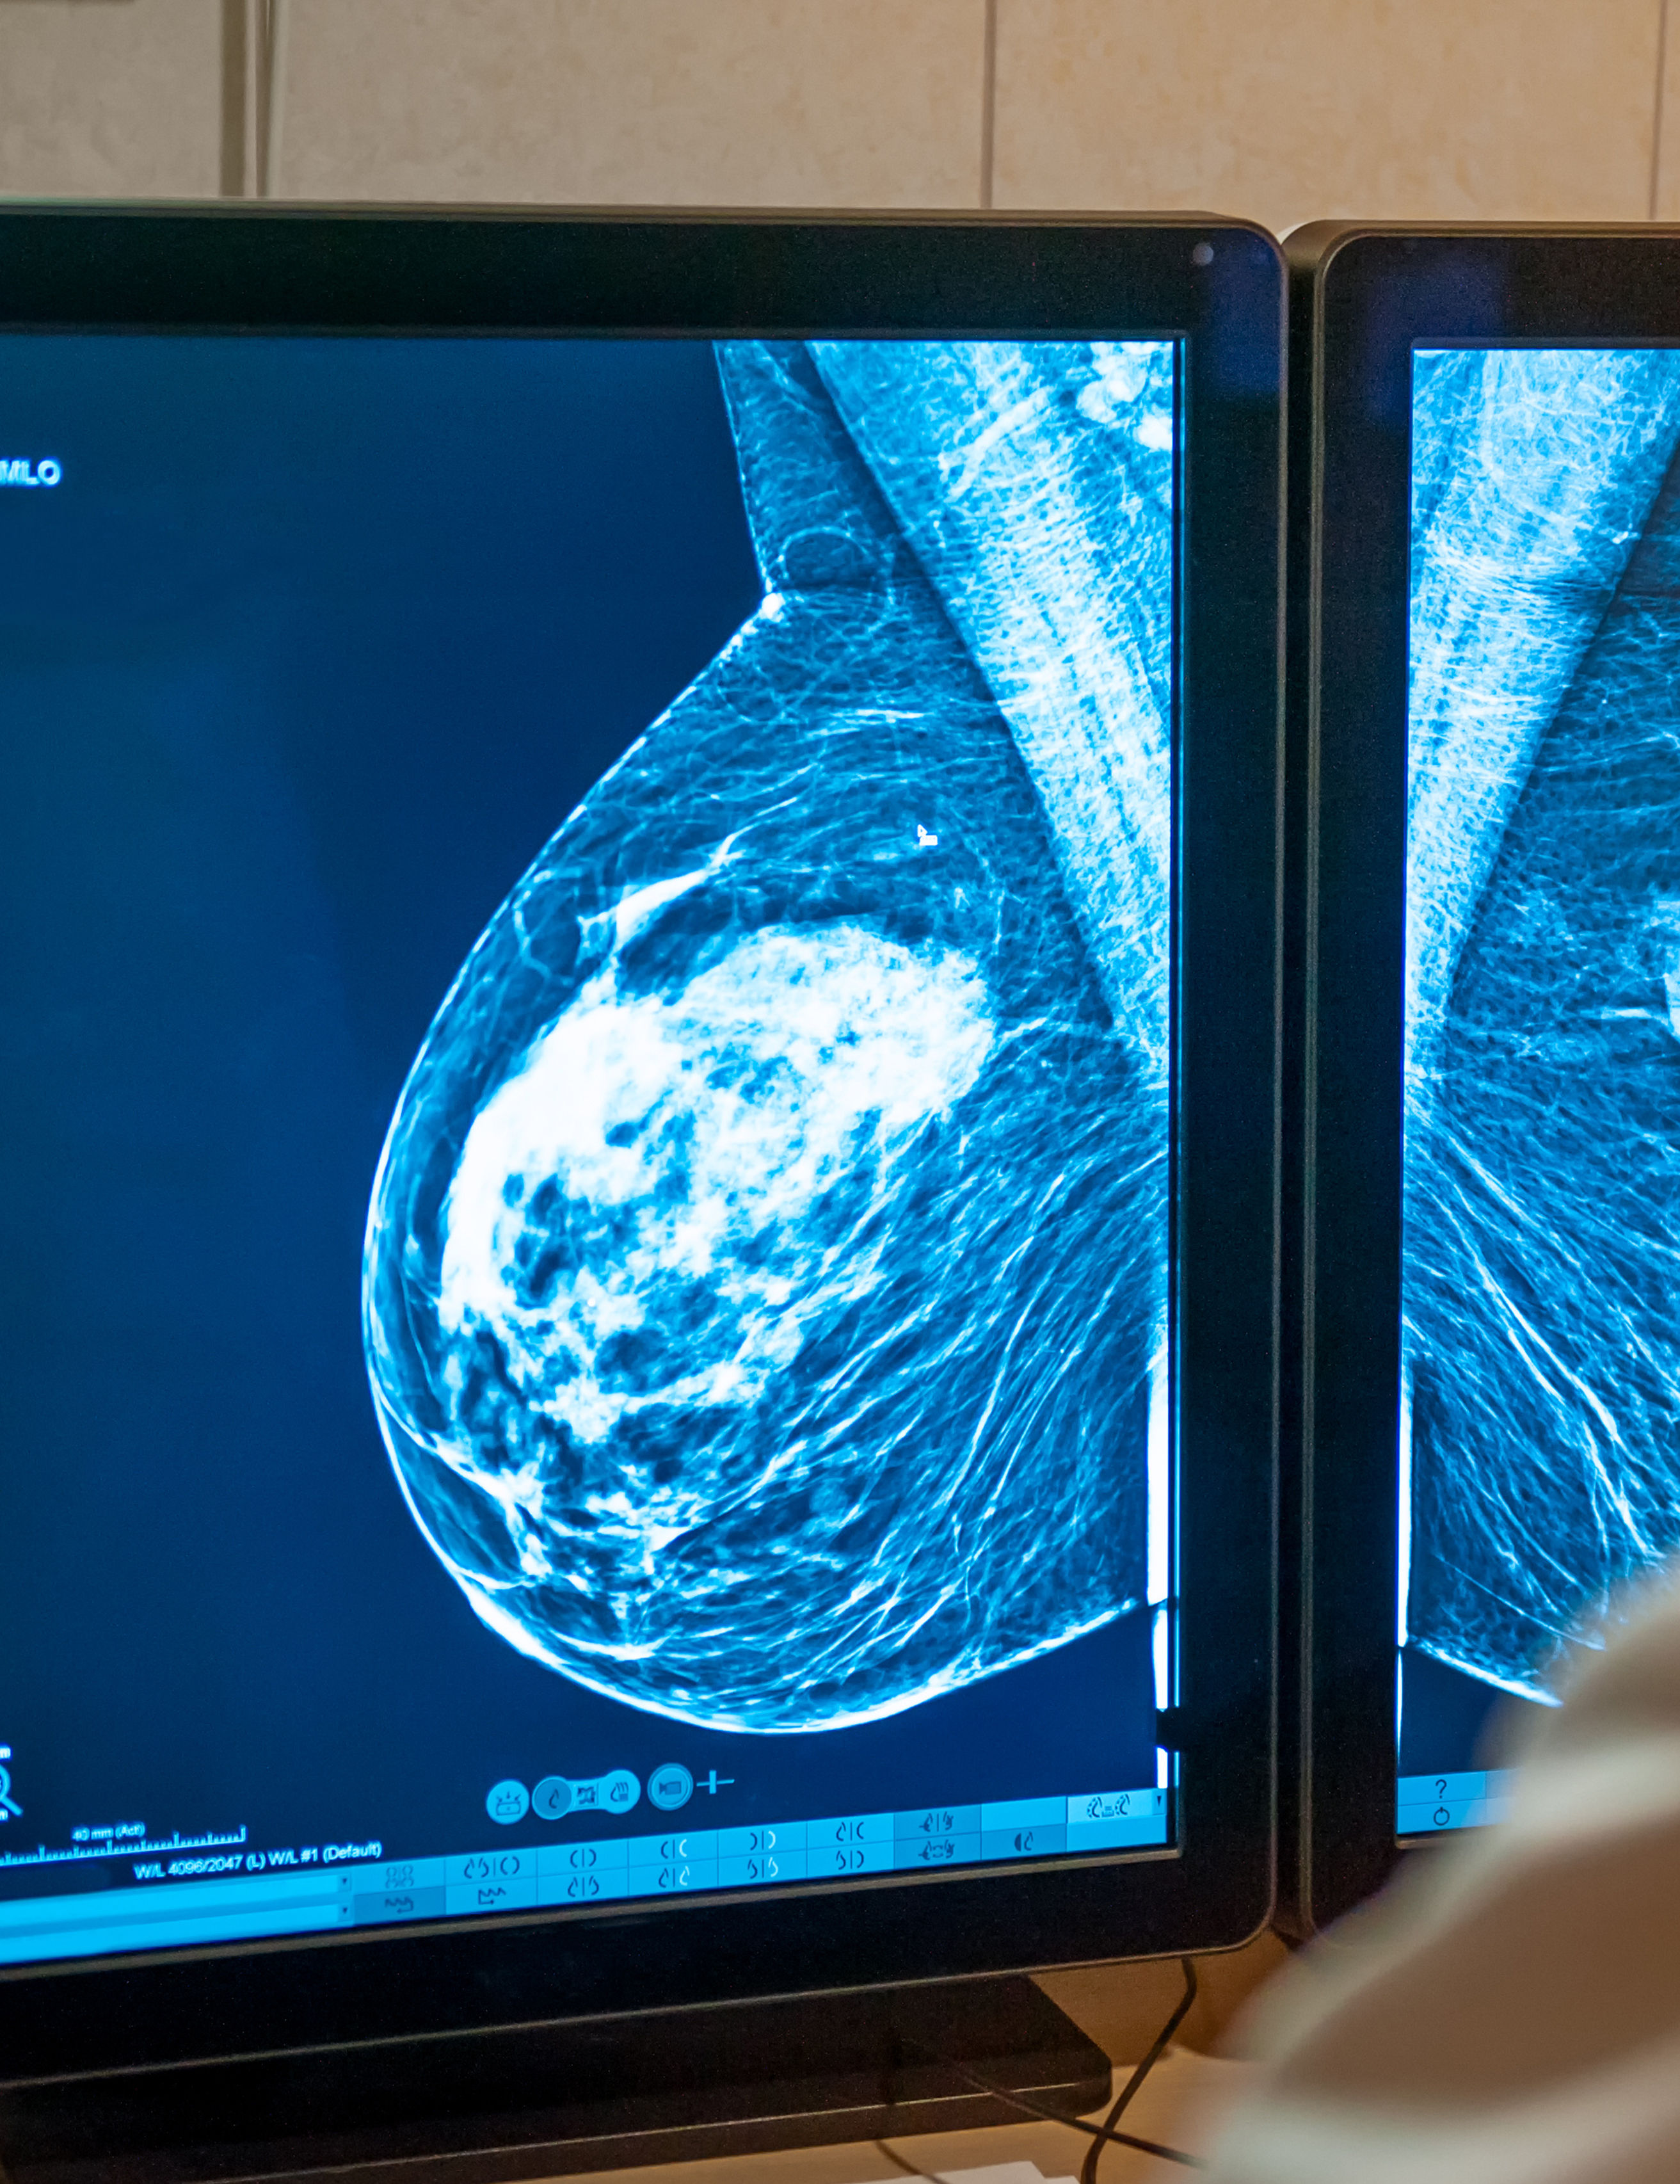

As women, we’re known for making sure everyone around us is taken care of. But all too often, taking care of ourselves is last on the to-do list. At CalvertHealth, we make a point to take care of you. We’ve got you covered with state-of-the-art imaging for your yearly mammograms, OB-GYN providers who expertly guide you through adolescence to motherhood and beyond, and the classes and education you need to live your best health. But we have your back for those tough days… when you need someone to talk to about depression, the motivation to work on issues like rebuilding your pelvic floor, or a whole team to support your fight with breast or ovarian cancer. No matter what phase of life or what health challenges you’re ready to conquer, we’re here for you.

This breast cancer survivor describes the journey to finding her new normal.